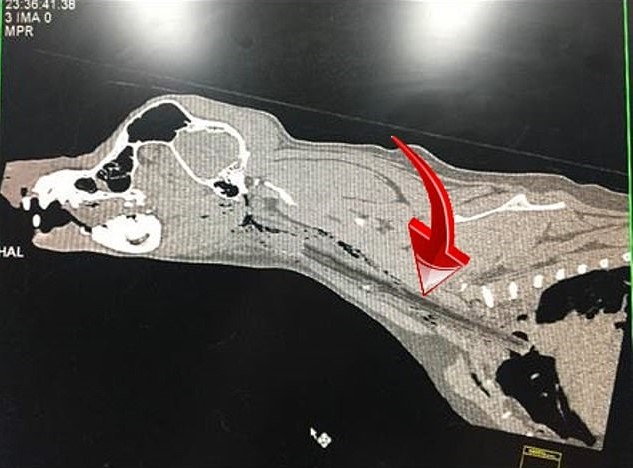

“X-rays soon revealed the culprit and Dash was immediately sent to us here at ARH Homebush for possible surgery.

“ARH Specialist Surgeon Dr David Simpson was called in late that night and a CT was performed to locate the exact location of the stick to prepare for surgery.”